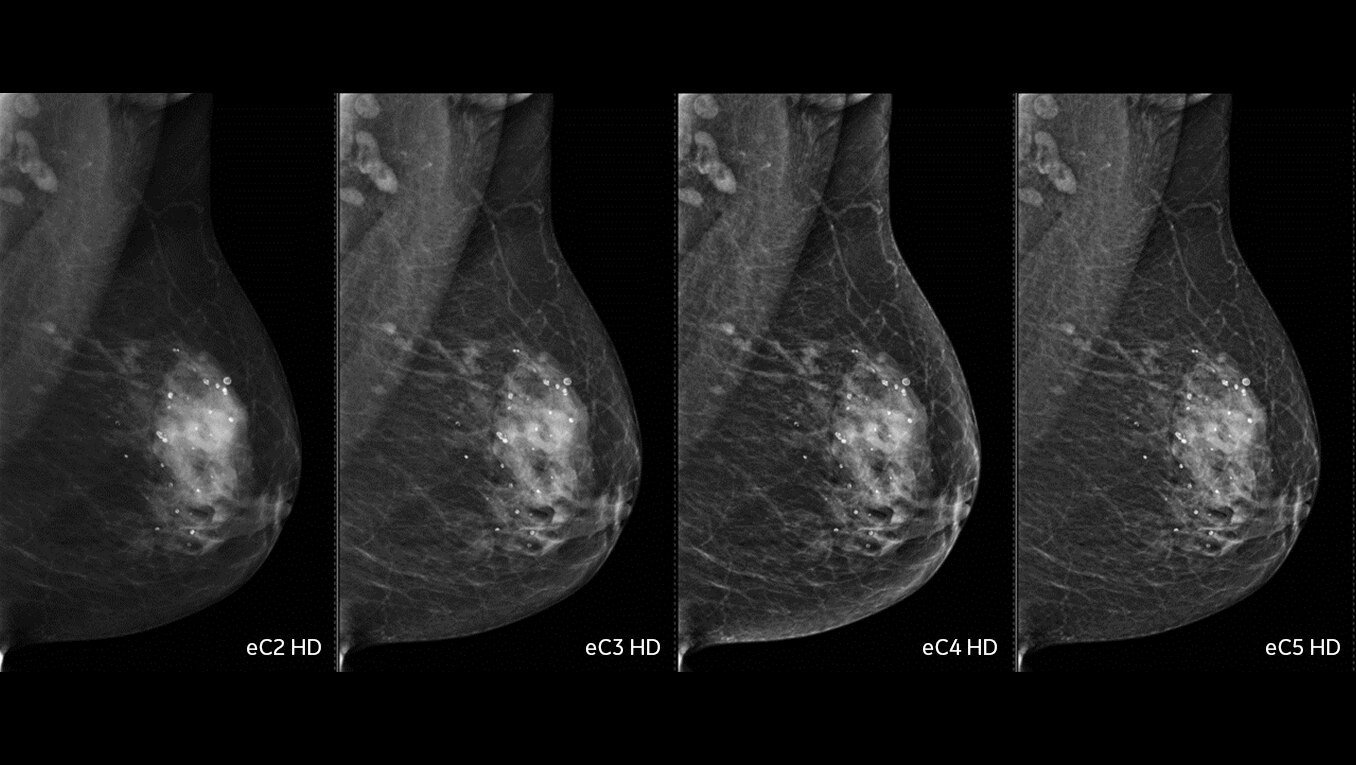

SenoBright™ HD

Contrast-Enhanced Mammography advanced application

Reduces the masking effect of breast tissue to reveal what matters1.